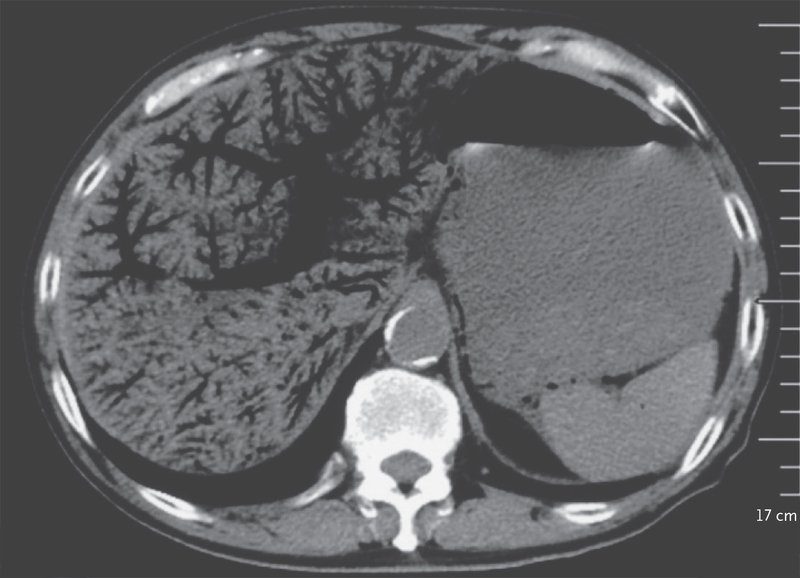

A 72-year-old man

👉presented to the emergency department with an 11-hour history of periumbilical abdominal pain and inability to pass flatus

What is the finding?

What is the most common underlying cause? Image

Portal Venous Gas

Bowel ischemia

Portal venous gas is most commonly associated with bowel ischemia

👉 poor prognostic sign in patients with that condition